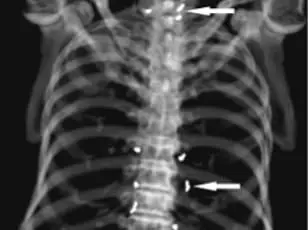

A 65-year-old woman in South Korea, seeking relief from osteoarthritis pain through alternative medicine, was left in shock when an X-ray revealed hundreds of gold threads embedded in her knees.

The discovery, made during a routine scan to assess her condition, raised urgent questions about the safety and efficacy of gold thread acupuncture, a practice increasingly used in Asia for pain management.

Doctors treating the woman, whose case was detailed in the *New England Journal of Medicine*, emphasized the diagnostic challenges posed by the threads.

On imaging, the specks clustered around her kneecaps and extended toward her shin and thigh, obscuring critical anatomical details. 'This case underscores a growing concern,' said one physician involved in the report. 'Alternative therapies like gold thread acupuncture can complicate medical imaging and delay proper diagnosis, especially when symptoms worsen unexpectedly.' The medical team did not specify whether the threads were removed, but experts warn that leaving them in place can lead to severe complications, including infections and organ damage if the threads migrate.